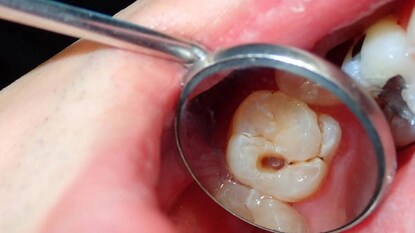

মুখের স্বাস্থ্যের ক্ষেত্রে, টুথব্রাশ কোনও প্রাকৃতিক ওষুধের চেয়ে কম নয়। মাড়ি থেকে রক্তপাত, ফোলাভাব, ব্যথা, পায়োরিয়া বা আলগা দাঁতের জন্য এটি অত্যন্ত উপকারী বলে বিবেচিত হয়। এটি মাড়ি শক্ত করে, ব্যাকটেরিয়া হ্রাস করে এবং দাঁতকে মূল থেকে শক্তিশালী করতে সাহায্য করে, দীর্ঘস্থায়ী জীবন নিশ্চিত করে। টুথব্রাশ জিহ্বা পরিষ্কার করতেও সাহায্য করে। ব্রাশ করার পর নিমের দাঁতনে দিয়ে জিভ পরিষ্কার করার ঐতিহ্য রয়েছে আয়ুর্বেদে দীর্ঘ দিন। জিভের সাদা আবরণ আসলে একটি বিষ, যা মুখের দুর্গন্ধ এবং অন্যান্য অনেক রোগের কারণ হয়। নিম, বাবলা, আপমার্গ, বট, খের বা অর্জুনের ডাল দিয়ে তৈরি টুথব্রাশকে সবচেয়ে উপকারী বলে মনে করা হয়। সঠিকভাবে টুথব্রাশ ব্যবহার দীর্ঘমেয়াদে আপনার স্বাস্থ্যের উন্নতি করতে পারে।